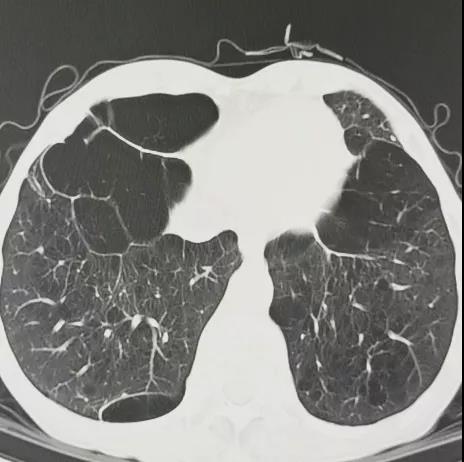

重度肺气肿、多发肺大泡 二叶瓣畸形伴左右冠瓣粗大融合嵴

患者男性,67岁,活动后胸闷气促4年余。术前心脏超声提示先天性二叶式主动脉瓣畸形伴极重度狭窄及轻度反流,峰值流速7.1m/s,峰值压差200mmHg,平均跨瓣压差118mmHg,瓣口面积仅0.5cm2。CT评估显示主动脉瓣为Type I型二叶瓣,瓣环面积569.4mm2,测算直径26.9mm。左冠脉开口高度19.4mm,右冠脉开口高度18mm(紧邻右无冠窦交界)。该患者为重度肺气肿伴多发性肺大泡,重度肺功能不全、贫血、低血小板、虚弱,STS评分9.3%,属于外科手术高风险。